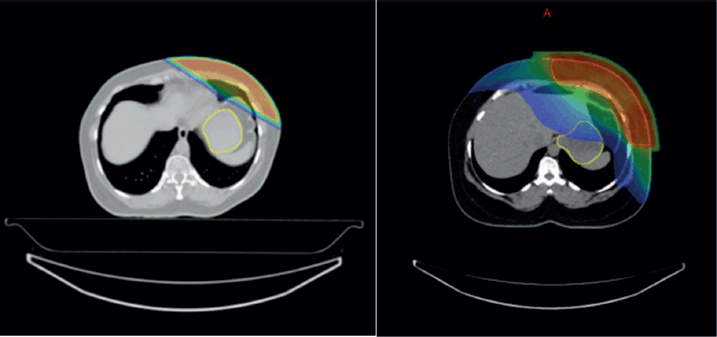

Further subgroup analysis using post hoc testing evaluated the association between radiation technique and upper GI toxicity, with significant differences observed among certain radiation techniques. Notably, patients treated with VMAT experienced slightly higher upper GI toxicity compared to those treated with 3DCRT with a mean difference of −0.815 (p = 0.000).

In contrast, no statistically significant difference was found in upper GI toxicity between 3DCRT and IMRT (p = 0.882) or between VMAT and IMRT (p = 0.083), indicating that IMRT does not significantly alter the toxicity profile compared to either 3DCRT or VMAT (Table 4) (Supplementary Figure 3a and b).

Supplementary Figure 3. (a and b): Isodose curves showing dose distribution between two RT techniques 3DCRT and IMRT.